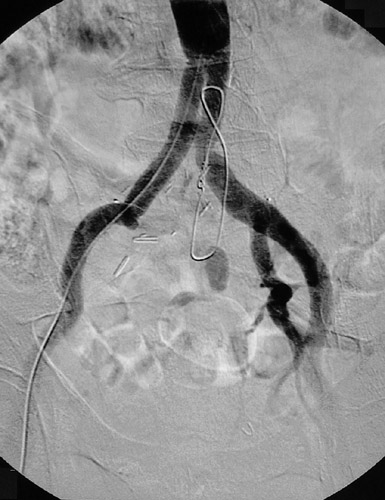

These aortogram views above and below demonstrate a right internal iliac artery occlusion in a patient who has had an aorto-biiliac arterial graft procedure.